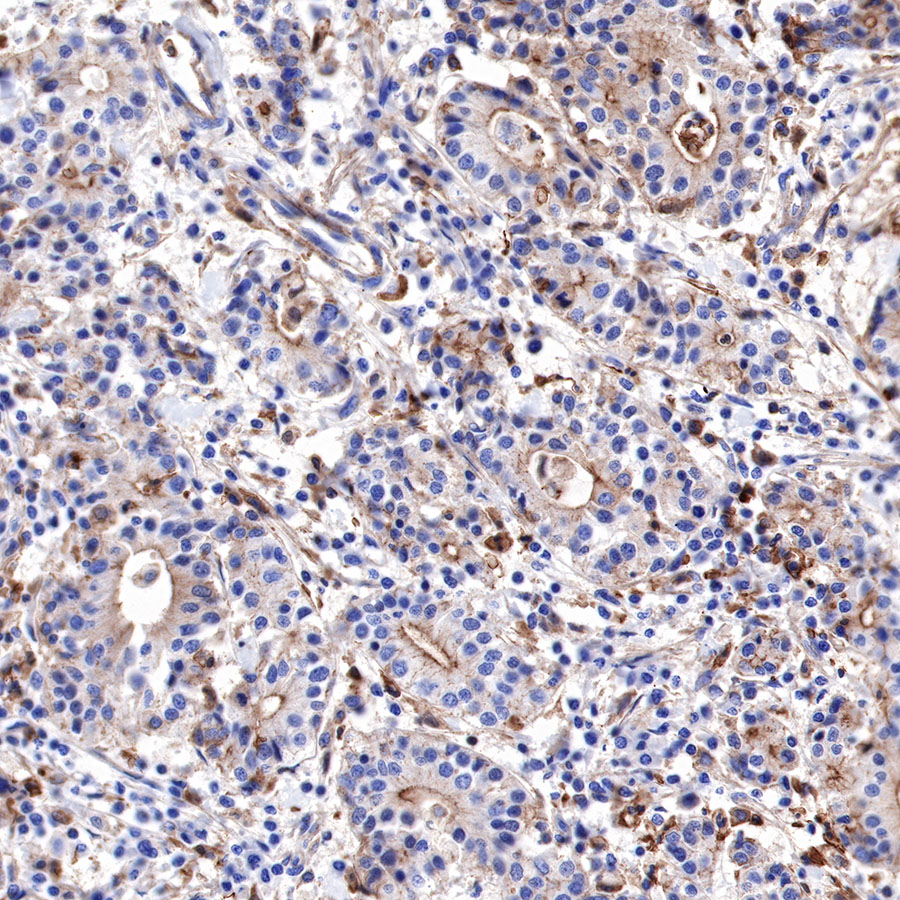

IHC shows positive staining in paraffin-embedded human pancreatic cancer. Anti-α-Actinin-1 antibody was used at 1/2000 dilution, followed by a HRP Polymer for Mouse & Rabbit IgG (ready to use). Counterstained with hematoxylin. Heat mediated antigen retrieval with Tris/EDTA buffer pH9.0 was performed before commencing with IHC staining protocol.